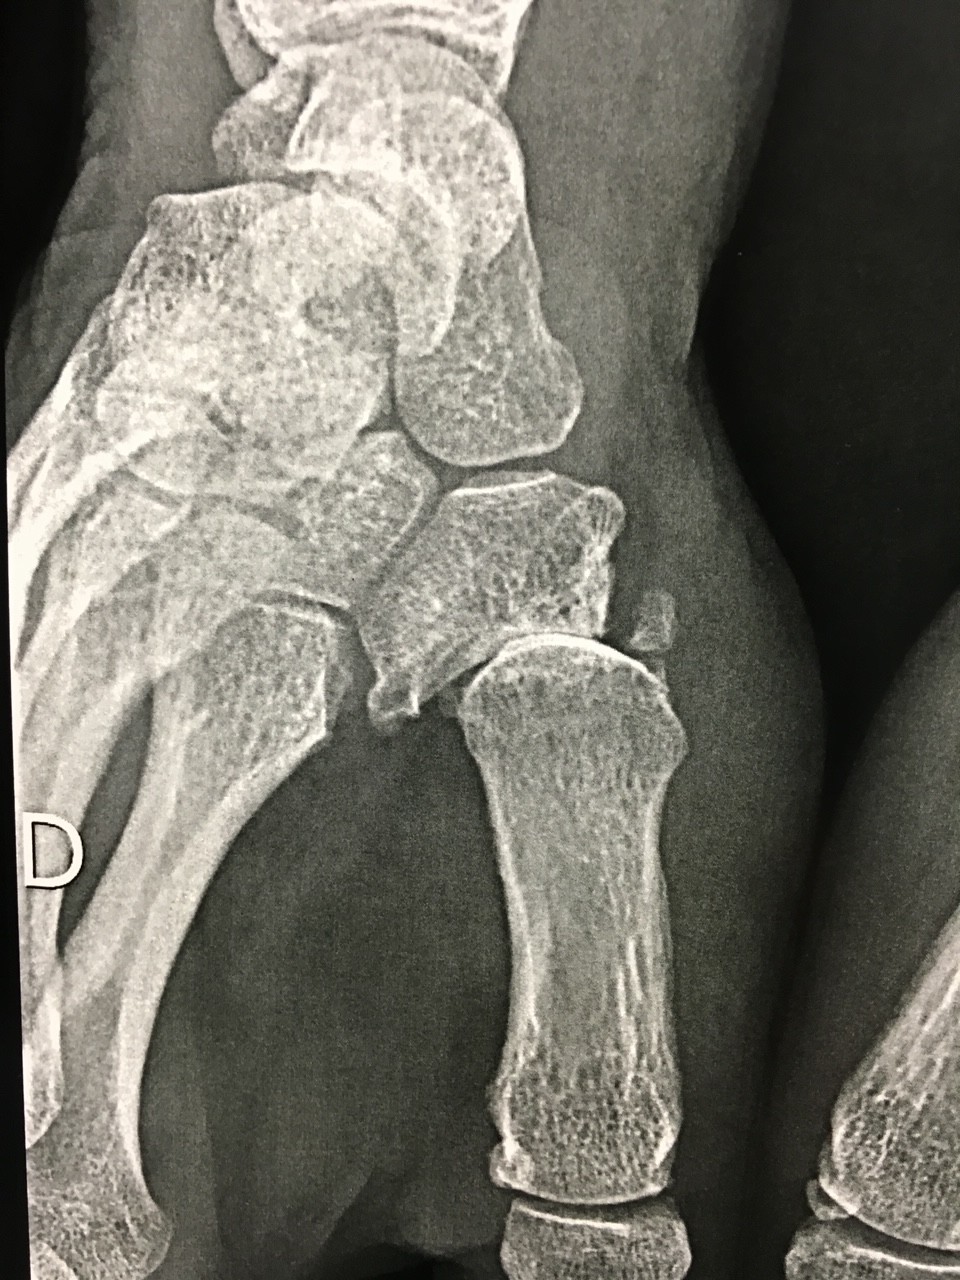

Le diagnostic se fait dès l’examen clinique. Les radiographies de l’articulation trapèzo-metacarpienne selon les incidences de Kapandji peuvent suffire dans la majorité des cas. Dans certains cas complexes, un scanner sera prescrit par le chirurgien. Un syndrome du canal carpien touche pratiquement un tiers des femmes concernées par l’arthrose de la base du pouce. Il est alors possible d’envisager le traitement des deux problèmes en même temps. Il est donc justifié de réaliser un électromyogramme dans le cadre du bilan avant traitement.